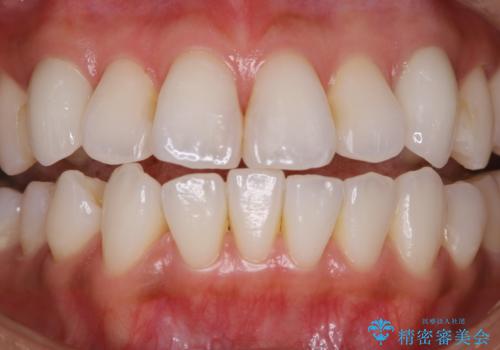

タバコによるヤニをPMTCで除去

担当医 歯科衛生士